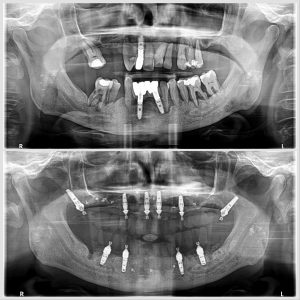

La cirugía guiada para implantes dentales es una técnica avanzada de implantología que utiliza imágenes 3D y software digital para planificar con exactitud la posición del implante antes de la cirugía.

En lugar de colocar el implante “a mano alzada”, el dentista diseña en el ordenador la posición ideal (ángulo, profundidad y ubicación). Después, se fabrica una férula quirúrgica personalizada que guía cada movimiento durante la operación.

- Se realizan radiografías y un escáner 3D (CBCT).

- El software simula la colocación del implante sobre tu hueso.

- El dentista elige la mejor posición y tamaño.